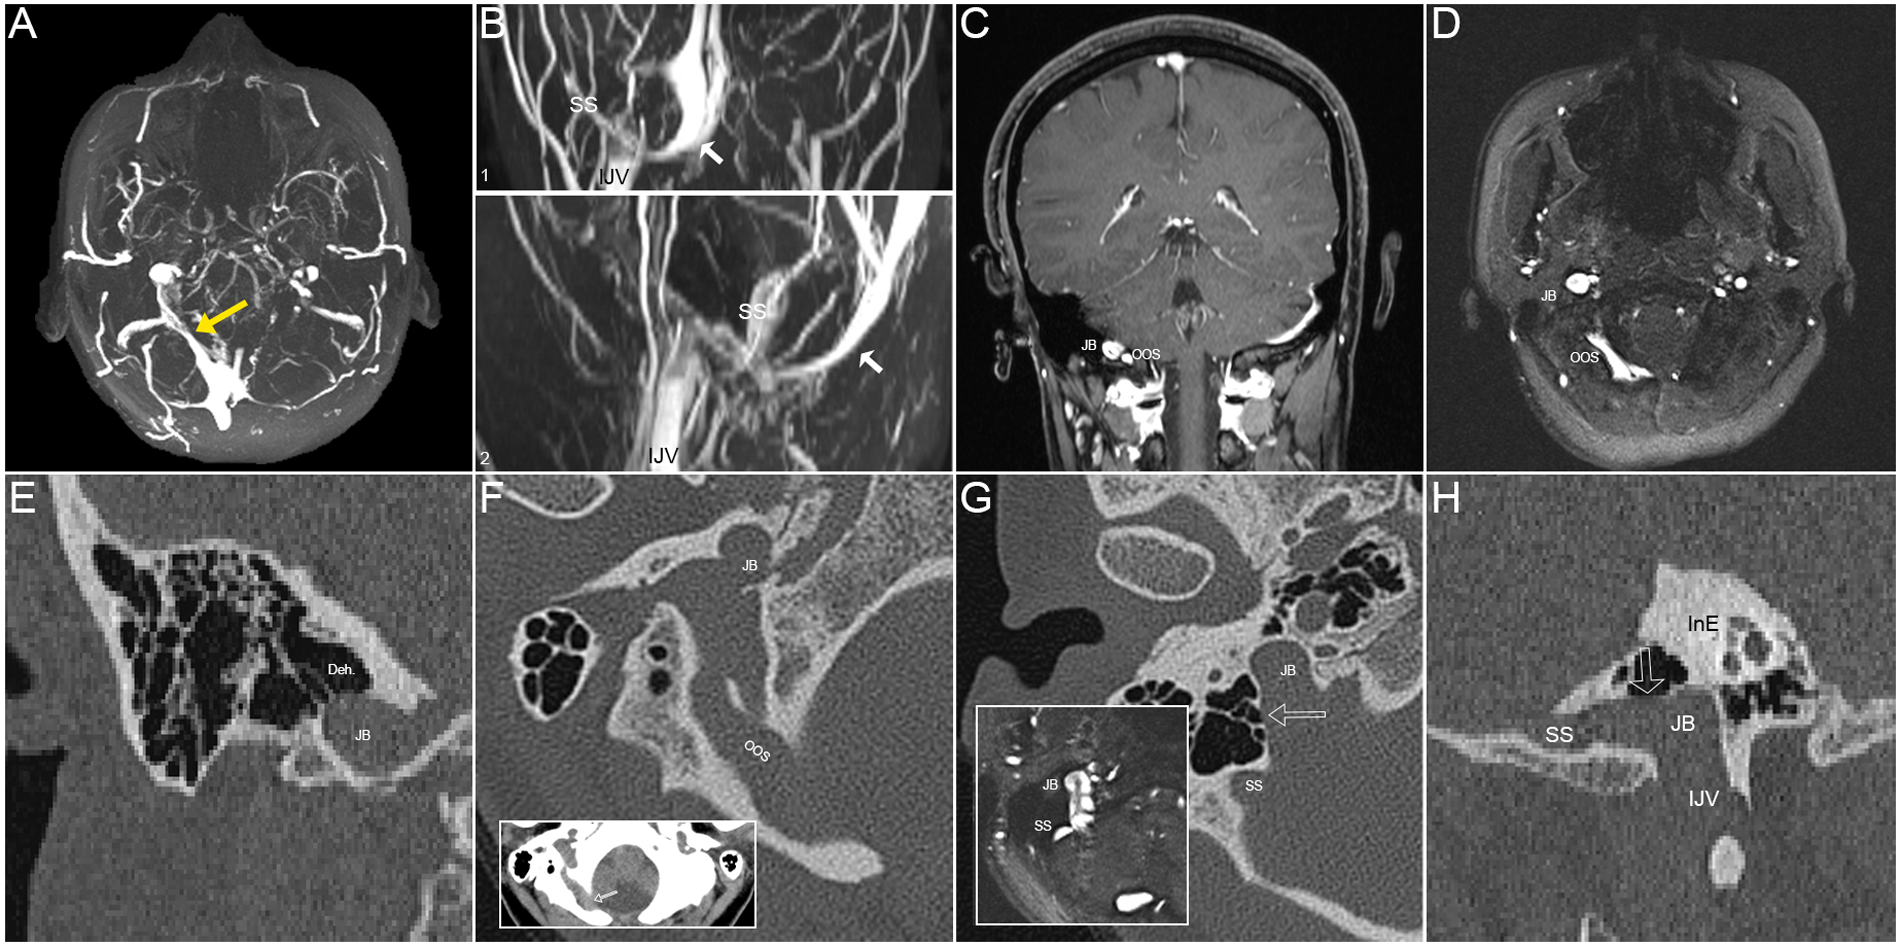

Figure 3

Radiological images of the patient in case 2 of right-sided pulsatile tinnitus (PT). (A) The maximum intensity projection (MIP) reconstruction of axial 2D-time-of-flight (TOF) magnetic resonance (MR) images showing an enlarged oblique occipital sinus (OOS) with distal stenosis (yellow arrow) anastomosing with the ipsilateral jugular bulb (JB). (B) (1) Coronal and (2) sagittal maximum intensity projection (MIP) reconstruction of 2D-time-of-flight (TOF) magnetic resonance (MR) images demonstrating the enlarged OOS (white arrows) running under the cerebellum. SS, sigmoid sinus; IJV, internal jugular vein. (C) Coronal contrast-enhanced T1-weighted gradient echo (2D FLASH) MR slice showing the relative locations of OOS and JB. (D) An axial 2D-TOF MR slice showing the SS, diverticulum (Div.), JB, and OOS. (E) Coronal CT image demonstrating dehiscence at the top of the SS-JB wall. (F) The notch of the OOS cuts through the edge of the foramen magnum of the occipital bone (red arrow). (G) Axial CT image showing SS-JB wall dehiscence and intrasinus flow pattern exhibited using the corresponding 2D-time-of-flight (TOF) magnetic resonance slice. (H) Reconstructed sagittal CT image exhibiting SS-JB wall dehiscence and locations of the SS, JB, and inner ear (InE).